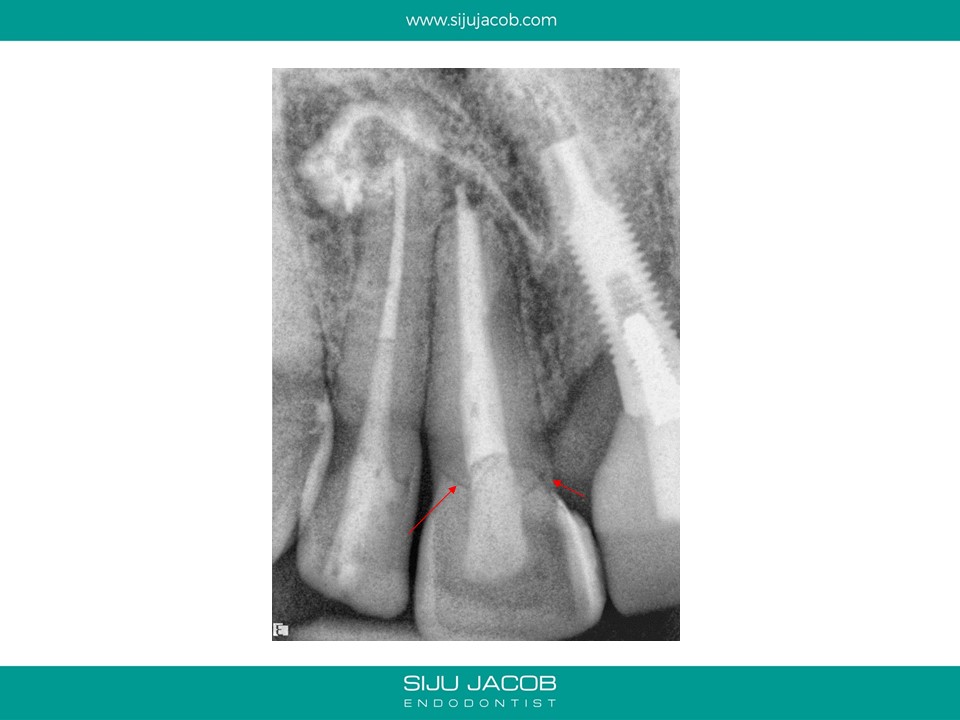

This patient was from The U.S. I re-treated a lateral incisor tooth of his while he was in Bangalore. He then went back to U.S. I received a mail from him two years later saying that the tooth we did was hurting. I thought that maybe, the lesion had recurred. I referred him to an Endodontist in the u.s who forwarded the radiograph to me. The lateral that I re-treated had healed well. It was an old central Incisor that had been treated much earlier that had fractured.